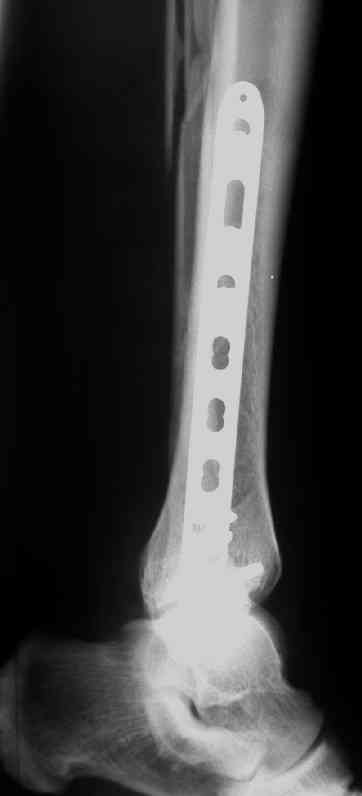

В приложении пример лечения аналогичного повреждения (плюс задний край).

Выполнил MIPO предизогнутой метафизарной LCP

Красиво получилось, поздравляю. Насчет немедленной полной нагрузки, как на гвозде, про что Алексей Семенистый говорит - будете разрешать сразу?

И все же немного критики:1) Вы добивались анатомичной репозиции, которая требует абсолютной стабильности, которая в свою очередь возможноа только в условиях межфрагментарной компрессии. Пластина уложена как мостовидная, не хватает стягивающнго винта. 2) есть укорочение малоберцовой кости, необхордимо восстановить ее длину! В таком виде я бы не стал разрешать раннюю нагрузку. Добавить самую малость: стягивающий винт и остеосинтез малоберцовой кости и больной может наступать сразу.